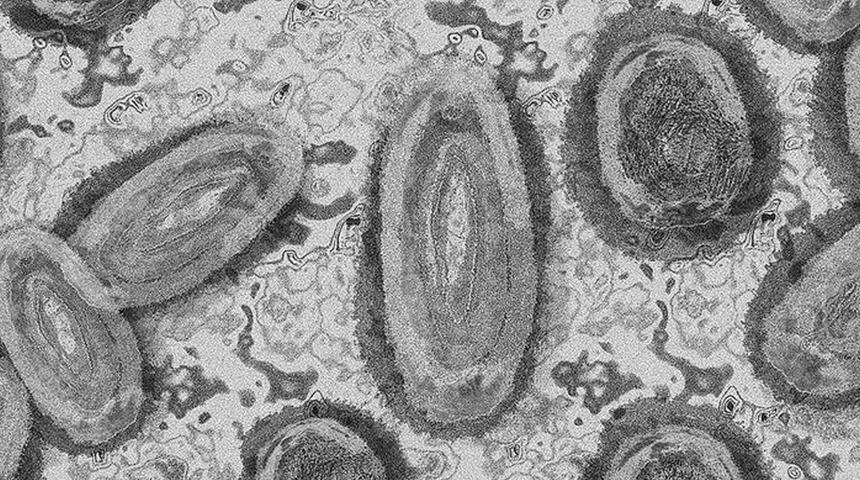

Endemik bir virüsün neden olduğu nadir hastalıklardan biri olarak bilinen maymun çiçeği, Kongo ve Batı Afrika türü olmak üzere ikiye ayrılıyor.

Genellikle hayvandan insana ve nadiren insandan insana yakın temasla bulaşan virüs, vücutta yüksek ateş ve kaşıntılı kabarcıklara yol açabiliyor.